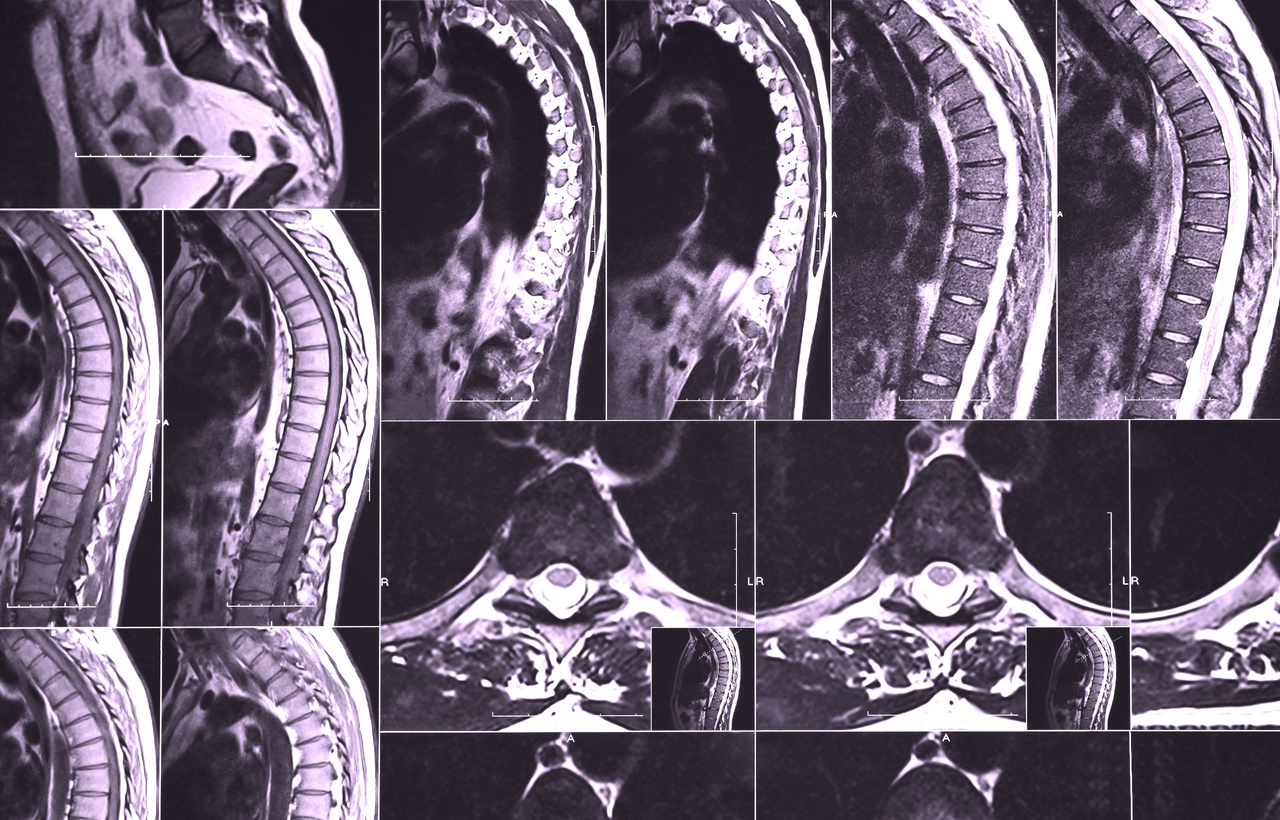

The most important diagnostic method is an MRI (magnetic resonance imaging) of the spinal cord . With MRI, the inflammation inside the spinal cord can be clearly seen, its extent and level assessed, and other causes of the symptoms, such as herniated discs or tumors pressing on the spinal cord, can be ruled out. This is critical for quickly initiating the correct treatment (often high doses of cortisone) and limiting permanent nerve damage.